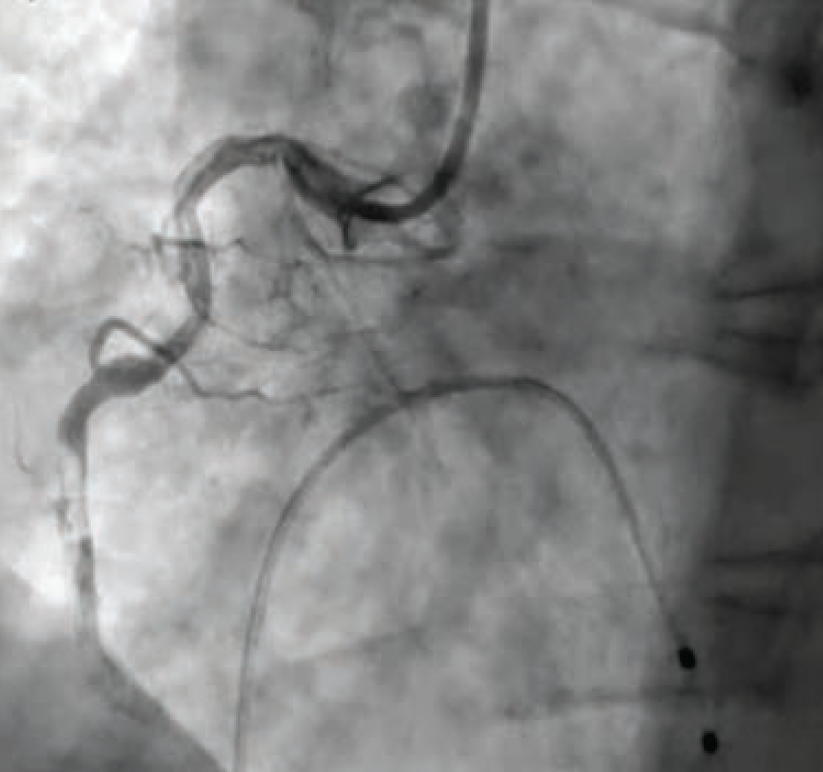

Once in the cath lab, the team of nurses and technologists worked swiftly alongside Dr. Case to first establish safe femoral access (ultrasound guidance and micropuncture technique) given the patient’s hemodynamic instability. Next, while promptly inserting a temporary venous pacemaker to address the patient’s complete heart block, the first episode of ventricular fibrillation occurred, and the first shock was successfully delivered. The team then placed an intra-aortic balloon pump (IABP) for cardiogenic shock management in the setting of right ventricular (RV) infarct. The operator used a 5 Fr Judkins left (JL)4 catheter to perform left coronary angiography and a 6 French hockey stick guide catheter for right coronary angiography. The patient was noted to have instent thrombosis (Figure 1), requiring mechanical aspiration thrombectomy (Penumbra). During the intervention, the patient experienced recurrent ventricular fibrillation. The cath lab team worked in unison to successfully deliver 19 shocks throughout the procedure, while administering several intravenous medications, including amiodarone, lidocaine, magnesium, bicarb, and Levophed (norepinephrine bitartrate), per the operator’s orders. Despite the critical arrhythmias and several interventions required to stabilize the patient, the team achieved a remarkable 49-minute door to balloon time in this case.

After successful thrombectomy, the delivery of a long stent was achieved by using a GuideLiner (Teleflex) guide extension catheter in the tortuous vessel. After stent placement, the patient was still having intermittent ventricular fibrillation. The Code Blue team, including intensive care unit (ICU) physicians and anesthesia, was called to be on standby for possible intubation due to recurrent arrhythmias. Fortunately, the patient remained awake, alert, and oriented (AAOx3), with oxygen saturations within normal limits on a non-rebreather. Dr. Case ballooned proximal to the stent and delivered nicardipine distally to restore flow throughout the vessel. A right heart cath was then performed to help guide management in the ICU following PCI.

Immediately following the procedure, the patient showed significant improvement in symptoms and was even cracking jokes with the cath lab team. Case findings included inferior ST-elevation myocardial infarction (STEMI), 1-vessel coronary artery disease — mid RCA 100% late stent thrombosis, complicated by ventricular fibrillation, complete heart block, and cardiogenic shock. The patient did not require mechanical support or pacemaker/implantable cardioverter-defibrillator (ICD), and remained hemodynamically stable. The patient’s cardiac rhythm stabilized and his heart function fully recovered. An echocardiogram the following day demonstrated preserved biventricular function with a left ventricular ejection fraction of 55% to 60% without wall motion defects. Troponins trended downward and he remained chest pain-free. The patient was discharged home 4 days after his initial STEMI presentation.